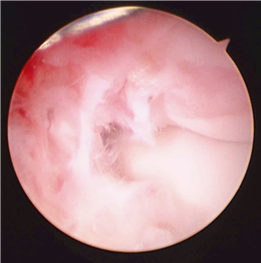

First MTP Arthrodesis

In cases of end-stage hallux rigidus, first MTP arthrodesis yields excellent, predictable outcomes. A dorsal longitudinal incision is made just medial to the EHL tendon. The joint is exposed, and aggressive cheilectomy is performed to remove all dorsal, medial, and lateral osteophytes. The remaining articular cartilage on the metatarsal head and the base of the proximal phalanx is resected using cup-and-cone reamers, which allow for infinite adjustment of the joint position prior to fixation.

Positioning of the fusion is the most critical step of the operation. The hallux must be positioned in 10-15 degrees of valgus, 15-20 degrees of dorsiflexion relative to the first metatarsal, and neutral rotation. Excessive dorsiflexion causes shoe impingement, while insufficient dorsiflexion leads to vaulting during gait and interphalangeal joint arthritis. Fixation is most reliably achieved using a pre-contoured dorsal locking plate combined with a lag screw crossing the fusion interface.

Image